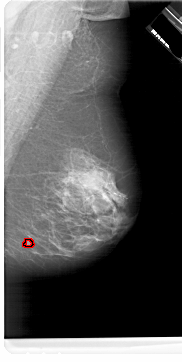

A_1622_1.RIGHT_MLO

RIGHT_MLO LINES 6871 PIXELS_PER_LINE 3451 BITS_PER_PIXEL 12 RESOLUTION 43.5 OVERLAY

FILE: A_1622_1.RIGHT_MLO.OVERLAY

TOTAL_ABNORMALITIES 1

ABNORMALITY 1

LESION_TYPE MASS SHAPE IRREGULAR MARGINS ILL_DEFINED

ASSESSMENT 4

SUBTLETY 2

PATHOLOGY MALIGNANT

TOTAL_OUTLINES 1

BOUNDARY